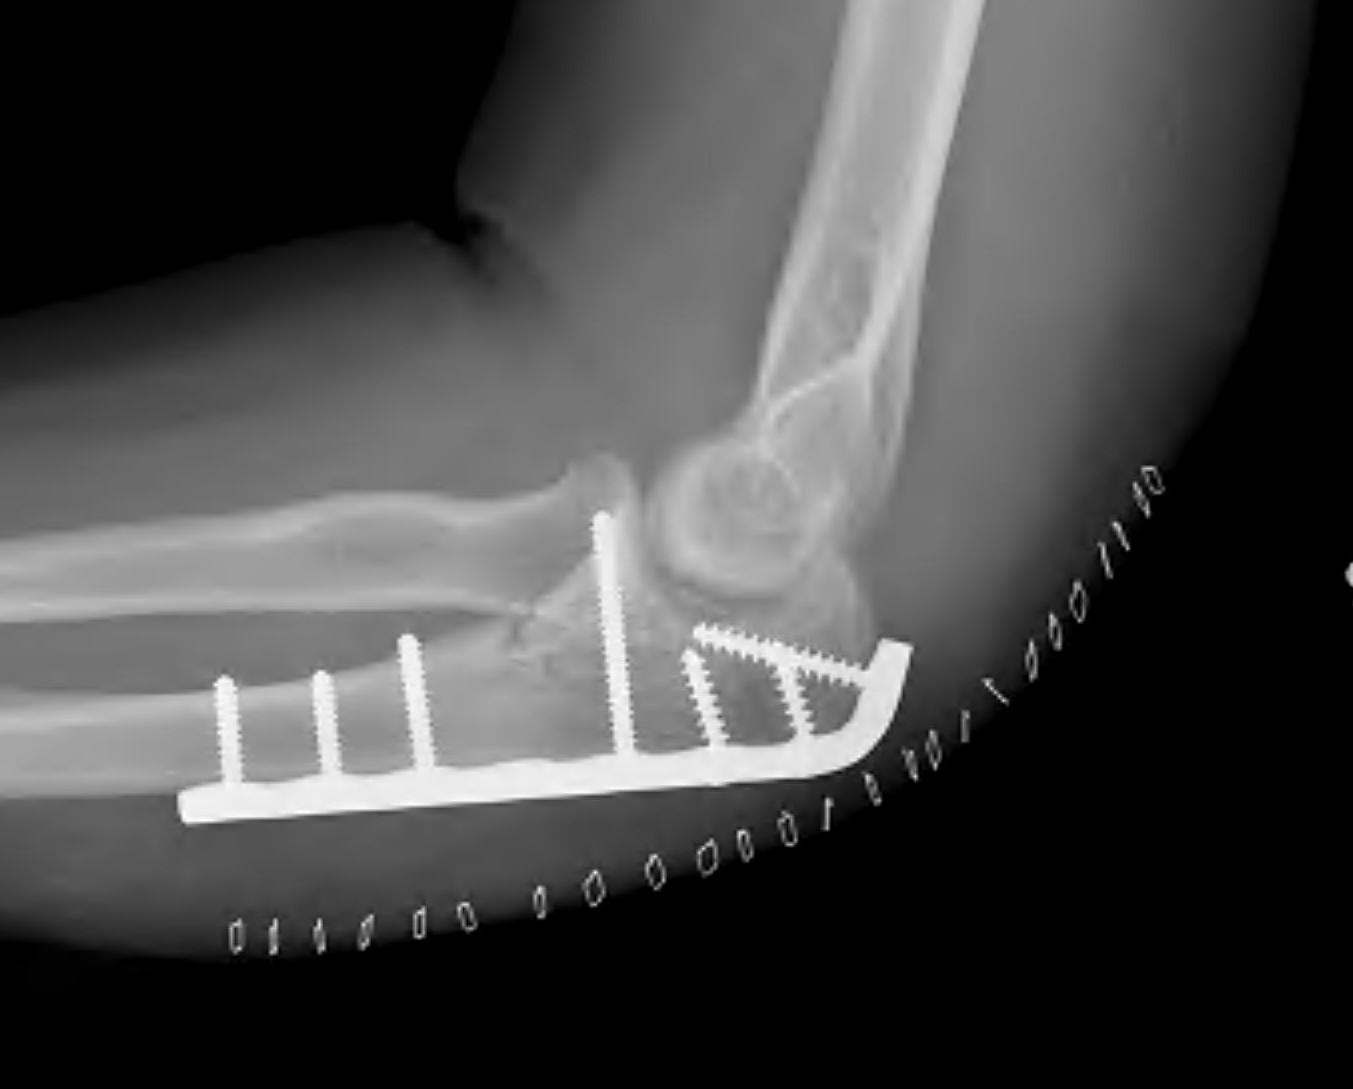

Olecranon plate + ORIF Type II coronoid process + radial head replacement

Olecranon plate with radial head replacement

Olecranon plate with radial head replacement + LCL repair

Olecranon plate + medial coronoid buttress plate + radial head replacement